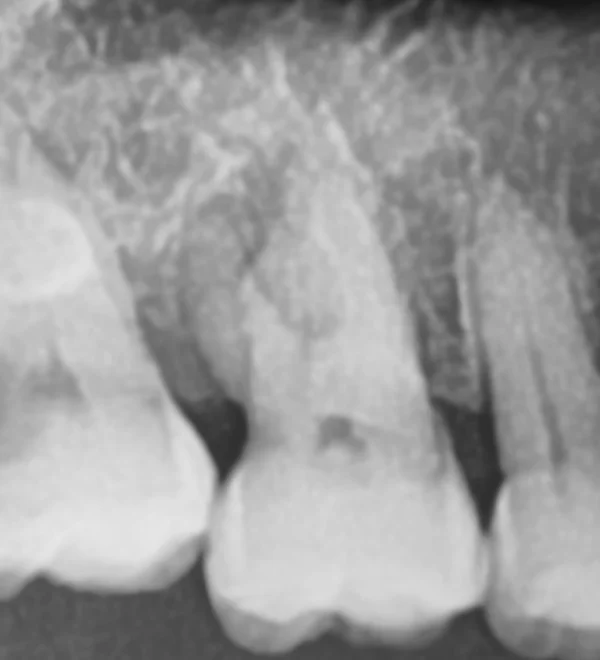

• Exercise 1

Dental x-ray, tooth and canal